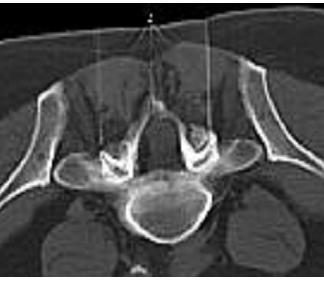

Das CT ist als Röntgenuntersuchung besonders geeignet für die Darstellung von Knochen. Weniger gut werden Bandscheiben und Nerven sichtbar.

Umgangssprachlich wird sie auch als die "kleine Röhre" bezeichnet, da die Gerätetiefe nur etwa 40 cm beträgt. Platzangst brauchen Sie hier nicht zu befürchten!

Nachteil ist die nicht unerhebliche Strahlenbelastung.

Der Patient liegt auf einem verschieb- baren Untersuchungstisch.

Röntgenröhre und Detektor werden kreisförmig um die zu untersuchende Körperregion gedreht.

Nur bei besonderen Fragestellungen ist es sinnvoll Kontrastmittel für eine CT-Untersuchung zu geben.

Ohne Übertreibung kann gesagt werden, daß die neurochirurgische Diagnostik mit Einführung der CT in den 70er Jahren eine neue Dimension erhalten hatte.

In der heutigen Generation stehen hochentwickelte CT- Geräte zur Verfügung.